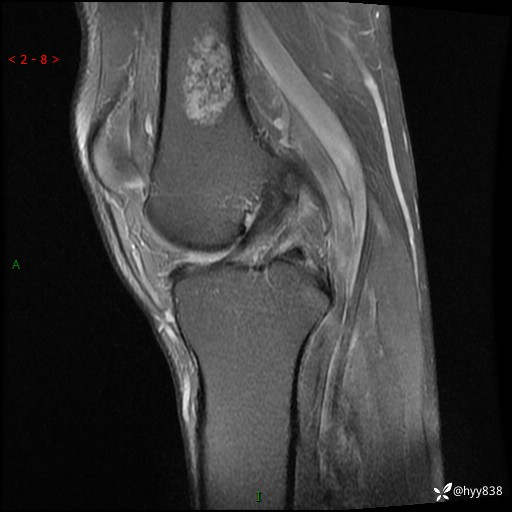

MRI

img

内生软骨瘤 (27)